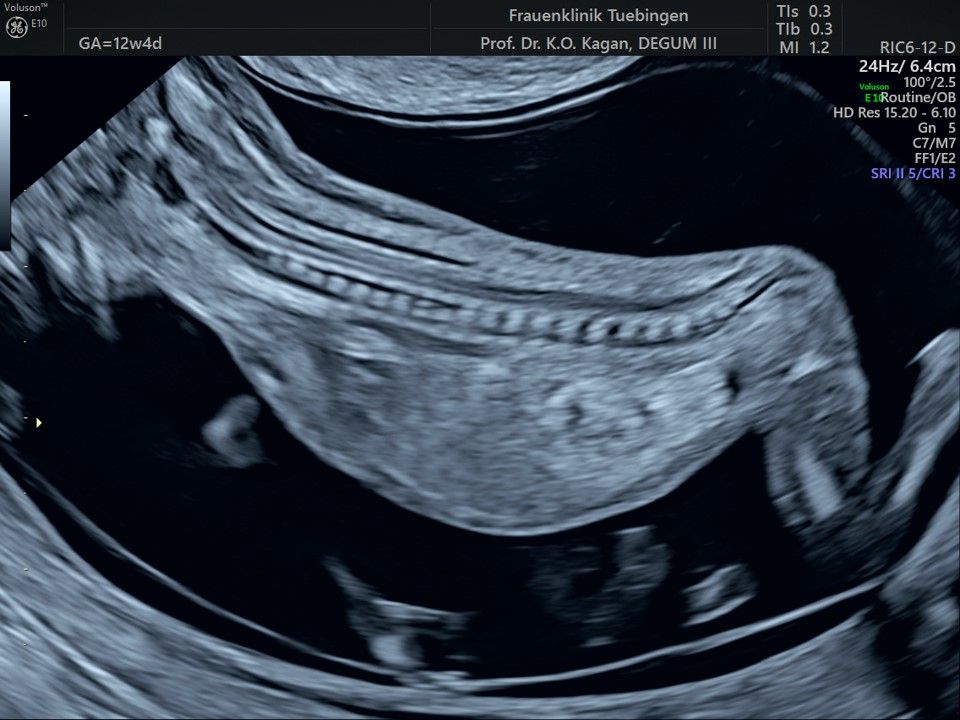

Im Rahmen des Ersttrimester-Screenings untersuchen wir die Organe des Feten mittels Ultraschall. Dabei machen wir auch gerne ein Bild für Sie.

Obwohl der Fet zu diesem Zeitpunkt erst zwischen 5 und 8cm groß ist, lassen sich bereits etwa die Hälfte aller schwerwiegenden Fehlbildungen erkennen bzw. ausschließen. Sollten wir eine Auffälligkeit sehen, werden wir mit Ihnen den Befund und das weitere Vorgehen ausführlich besprechen.

Herz

Das Ergebnis der Ultraschalluntersuchung ist wegweisend. Dabei wird der Fet vermessen, die Organe werden untersucht und die sonographischen Marker zur Risikoberechnung für Chromosomenstörungen werden beurteilt. Das sind: die Nackentransparenzdicke, Nasenbein sowie der Blutfluss in der rechten Herzhälfte und im Ductus venosus, einem Gefäß in der Leber des Feten.